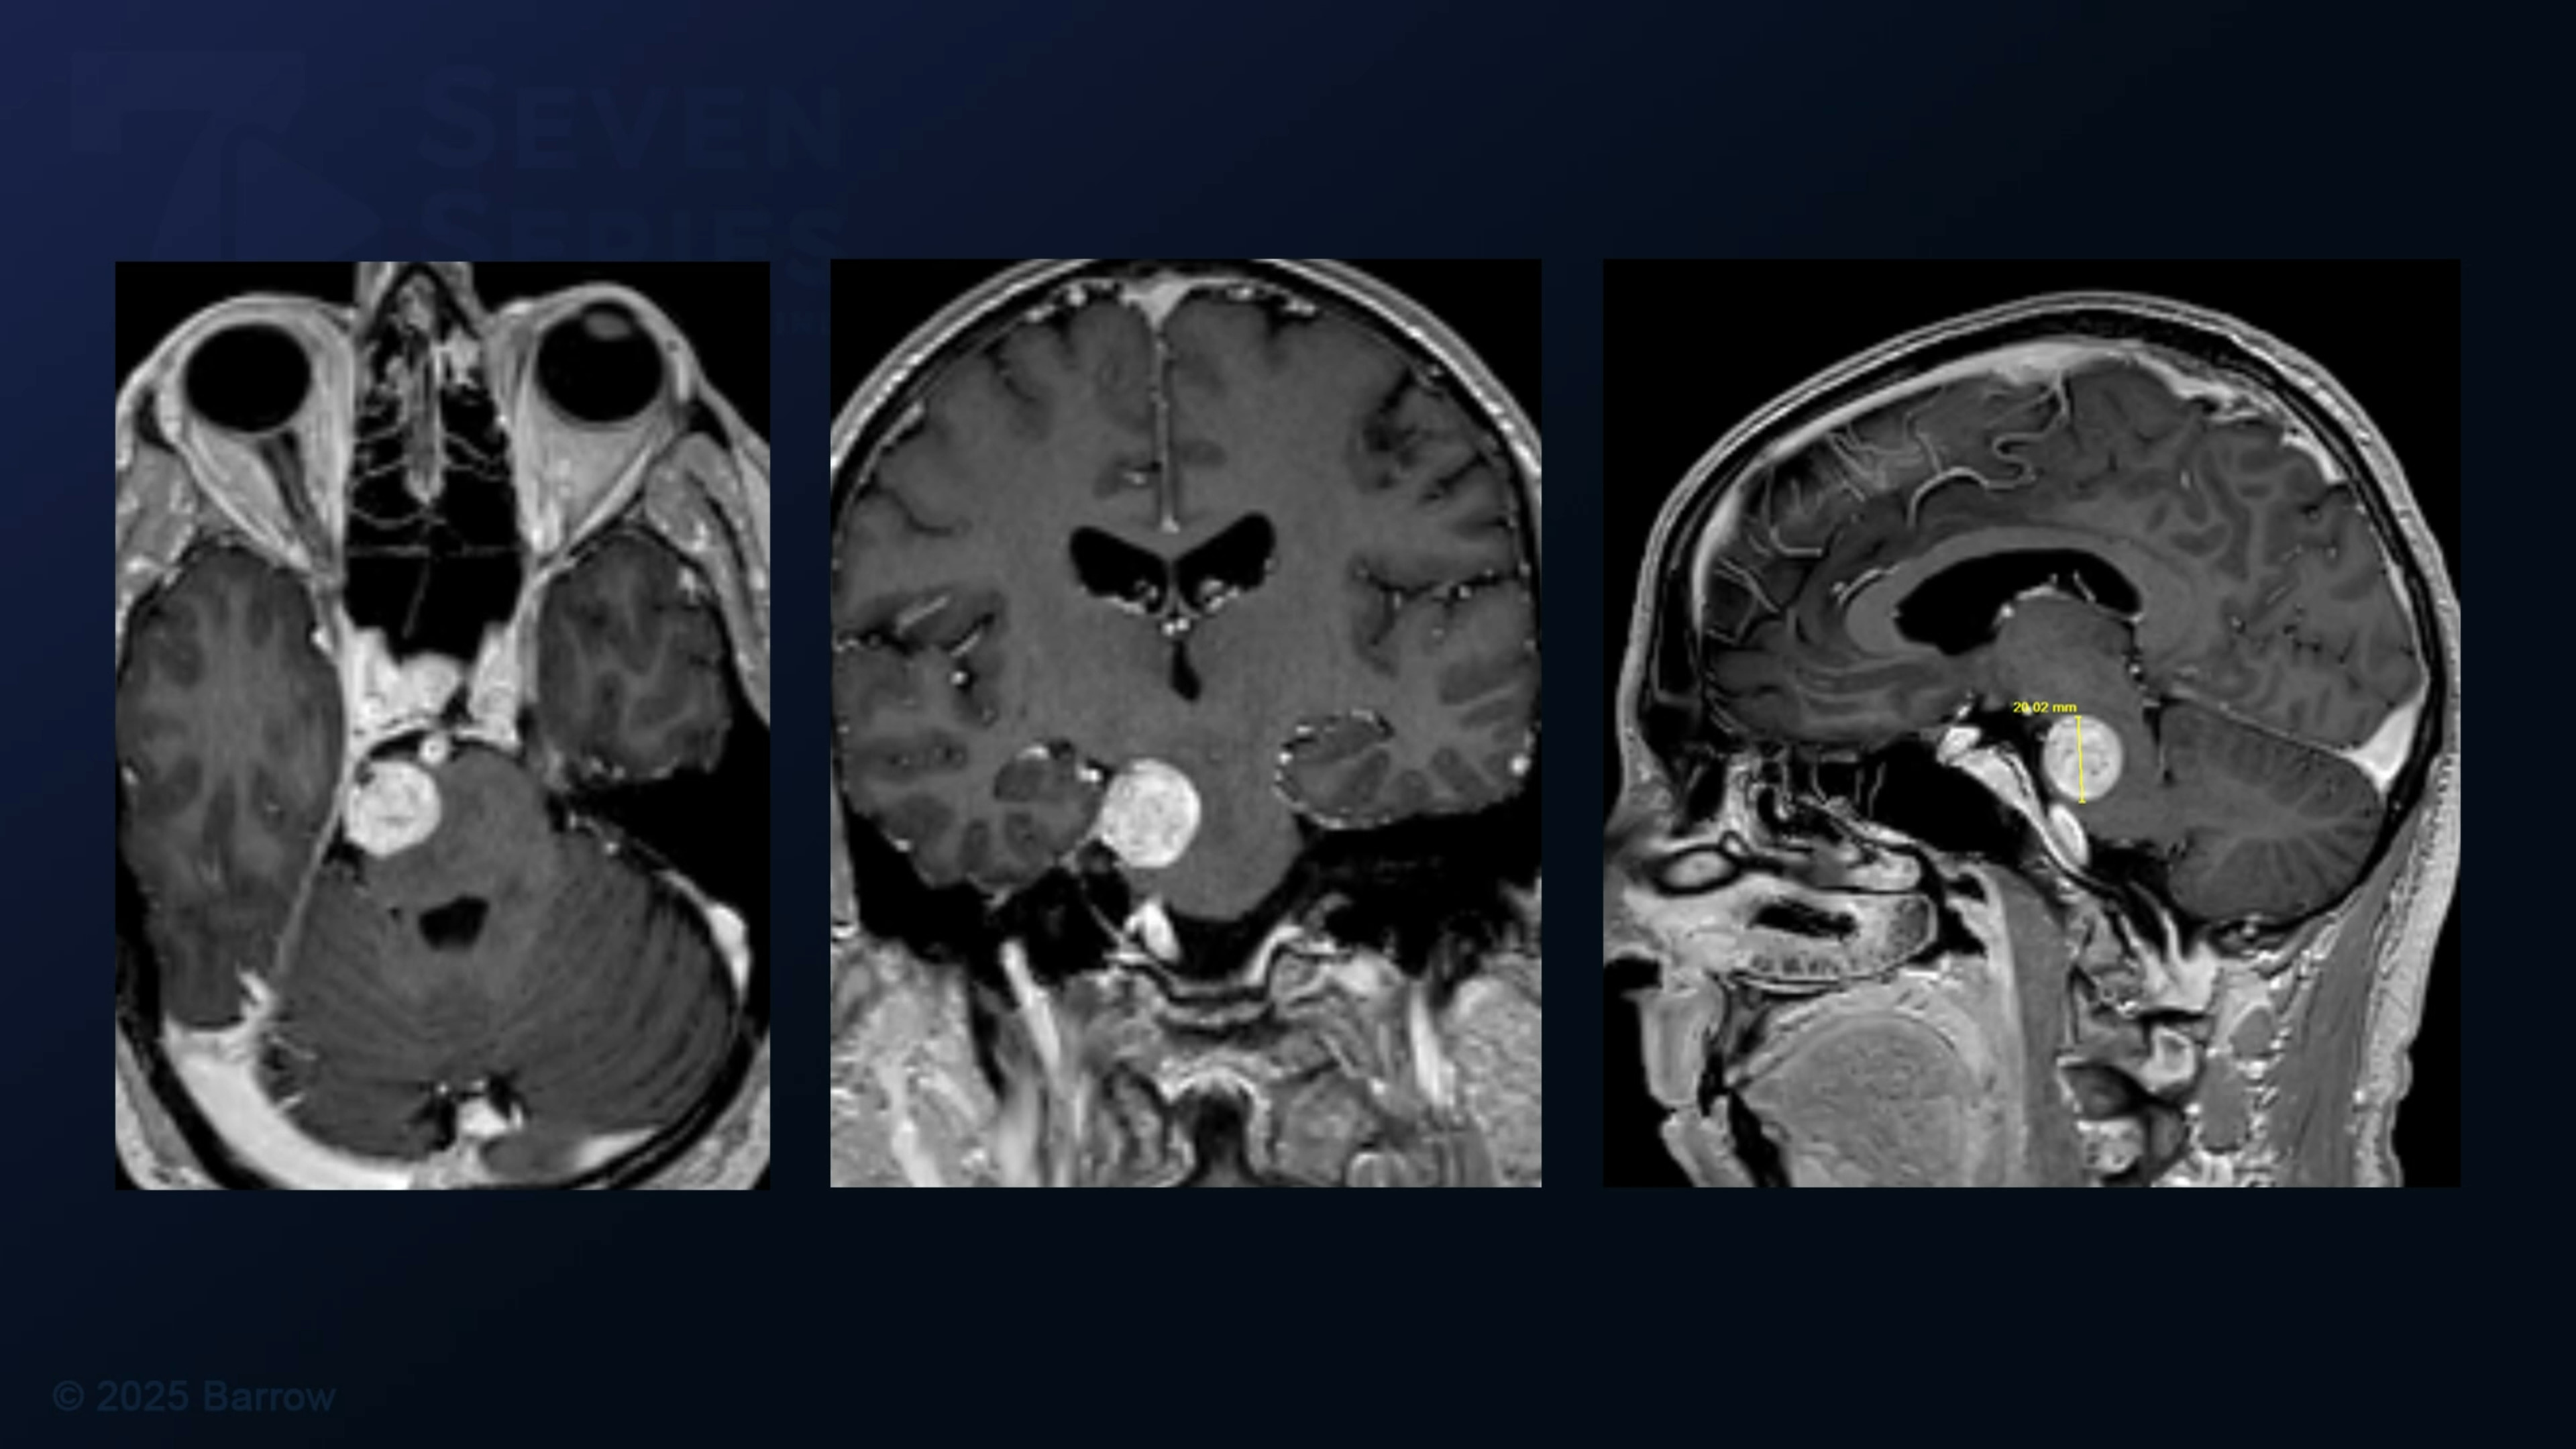

Episode 492 of Seven Series shows an extended retrosigmoid craniotomy for resection of a trochlear nerve schwannoma.